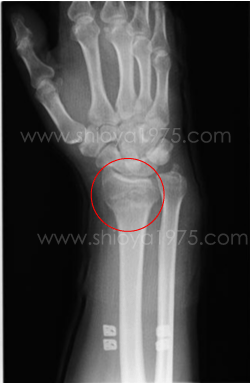

| 整骨(柔道整復)治療の一例をご紹介致します(X線写真掲載は患者様の同意を得ています) | |

| @右橈骨遠位端骨折・colles骨折・・・50代男性 | |

| 整復前(正面) | 整復前(横) |

| 整復後(正面) | 整復後(横) |